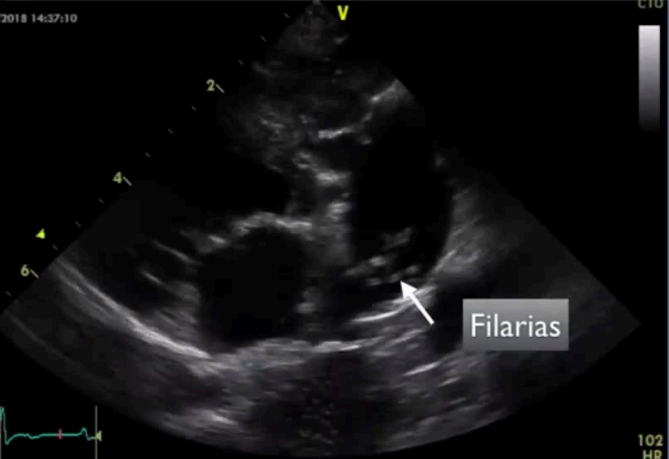

Patologías más frecuentes